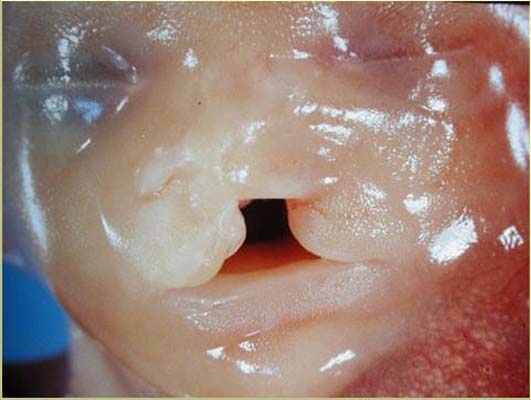

Tératome cervical macro